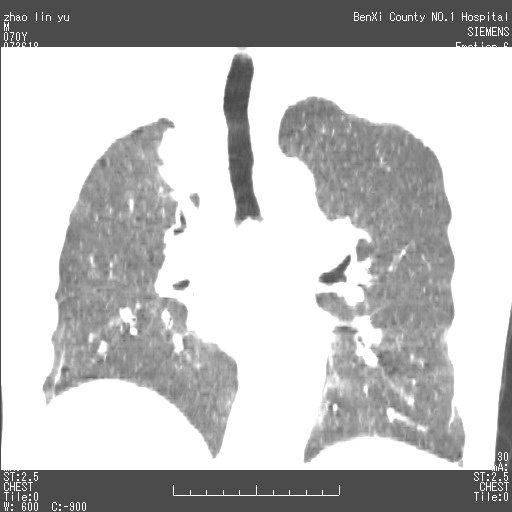

以下是引用王靖旗在2007-7-10 17:12:00的发言:[br] 男、70、咳嗽两个月,半年前换瓣手术,胸片未见异常,于昨天行x片发现右肺上野大片影,行ct扫描,这里是减薄图像,余肺正常。明天晚上会有增强扫描片,到时我会上传。[br][br] 冠状位请大家细看,应该是有意义的,[br][br] 请大家先看平扫发表意见。[br][br]

[br]冠状面[br]